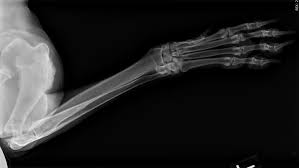

Signs Of Bone Cancer In Dogs Leg - Canine Bone Cancer The Big Story On Osteosarcoma In Dogs My Brown Newfies : Limping or lameness (most often the first to manifest). Osteosarcoma is the most common bone cancer in dogs. Sometimes a biopsy is performed by taking a small piece of bone and testing it. Osteosarcoma is a word derived from osteo, meaning bone, and sarcoma, meaning cancer. Favoring a leg can indicate many things from bruising, minor strain, ligament damage or rupture, arthritis, fracture … and yes, cancer. Lameness, which can be intermittent or constant

Symptoms of bone cancer in dogs: It commonly strikes large dog breeds between middle age and the senior years, but it has been known to affect dogs as young as two. Osteosarcoma usually develops deep within the bone. As the tumor continues to grow, the bone containing the tumor will expand. Or a small lump on the leg that becomes tender to the touch.

Top 10 Warning Signs Of Cancer In Pets Hudson Veterinary Hospital from www.hudsonvet.com (most dogs with this kind of cancer do not survive beyond a year with amputation alone. He is a 9 1/2 yr old english mastiff with a heart of gold! Lameness caused by osteosarcoma is typically mild at the onset, but then progresses over time. Tumor growth destroys healthy tissue, causing the bone to swell. They are most common in leg bones, but can affect any bone in the body. Washington ( circa) — osteosarcoma (osa) is one of the most common forms of bone cancer seen in veterinary patients. As the tumor grows and damages surrounding bone and tissue, your dog may start to show signs including: Dog bone cancer warning signs sometimes bone cancer makes a sudden appearance as a lump in the leg, or in worst case scenario, as a pathologic fracture.

Most dogs will show signs of swelling and soreness in limbs close to joints. Since we can't ask our dogs how they are feeling each day, it's important to understand the signs of a sick dog. This is a major operation, and the serious complications rate is up to 5%, with a fatality rate of less than 1%. In addition, it depends on the primary site of the tumor. Some of the signs that it's time to say goodbye to a dog with cancer include: Most commonly, it affects the long bones of the legs. A type of bone cancer called osteosarcoma is the most common type of primary bone cancer in dogs, accounting for over 95% of all bone tumors. The early signs of bone cancer in dogs can difficult for pet parents to recognize since symptoms tend to be subtle. Symptoms of bone cancer in dogs: Canine bone cancer symptoms osteosarcoma tumors typically form in a dog's long bones, or growth bones, and are found frequently below the elbow or near the knee or shoulder. Leg amputation surgery in pets. The cancer usually originates inside the bone and spreads to the outside of the limb. Lameness caused by osteosarcoma is typically mild at the onset, but then progresses over time.

Shrinking Tumors Nonsurgically Parsemus Foundation from www.parsemus.org This is a major operation, and the serious complications rate is up to 5%, with a fatality rate of less than 1%. Canine bone cancer symptoms osteosarcoma tumors typically form in a dog's long bones, or growth bones, and are found frequently below the elbow or near the knee or shoulder. If you decide to proceed with amputation, you will admit your pet into the hospital either the day before or the morning of surgery. Osteosarcoma is a common dog cancer in large breeds, and it most often affects the long bones of the legs. Symptoms and types many signs of bone cancer are subtle. The most common clinical signs noted in patients with osteosarcoma is lameness. Lameness may be acute or chronically progressive. One of the hallmark signs of canine osteosarcoma in the limb is pain, causing the dog to limp.